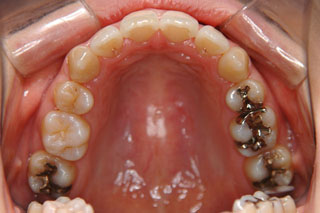

2年半ほどの治療で、装置を撤去し保定治療に移行しています。概ね緊密な臼歯の咬合と前歯の被蓋が確立されました。

保定治療を開始してから2年半が経過していますが、良好な咬合の安定が維持されています。見た目だけではなく、中心位マウントの咬合器にて顎位のズレを計測していますが、計測値は1mm未満の数値である事を確認しています。理想的には中心位=咬合位かも知れませんが、多少の遊びは必ず出てきます。しかしながら最初からルーズなゴールを目指していたら、的を外してしまうでしょう。できれば、ピンポイントで理想を目指したいものです。